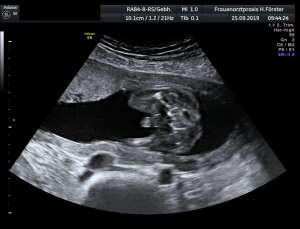

Gynäkologische Grundversorgung Frauenärztliche Krebsfrüherkennungsuntersuchung Nachsorge und supportive Therapie bei bösartigen gynäkologischen Tumoren Impfungen Brustultraschall Ultraschalluntersuchung der weiblichen Genitalorgane Psychosomatische Grundversorgung Chlamydienscreening FOB-Test (früher Hämoccult) Kontrazeption Geburtshilfliche Grundversorgung Geburtshilflicher Basisultraschall Erweiterter Basisultraschall (Organscreening) zw, 18-22.SSW Doppler/Duplexsonografie des fetomaternalen Gefäßsystems Infektionsscreening in der Schwangerschaft CTG (Kardiotokographie) Gynäkologische Grundversorgung Dies umfasst die Abklärung und Behandlung gynäkologischer Erkrankungen. Eine große Rolle dabei spielt das ärztliche Gespräch, ergänzt bei Notwendigkeit durch die gynäkologische Untersuchung oder Untersuchung der weiblichen Brust. In vielen Fällen werden noch Zusatzuntersuchungen durchgeführt (z.B. Ultraschalluntersuchungen, Abstrichentnahmen, Blutentnahmen) oder weiterführende Untersuchungen veranlasst (z.B. Röntgenuntersuchungen). >> zurück << Frauenärztliche Krebsfrüherkennungsuntersuchung Die Krebsfrüherkennungsuntersuchung der Frau ist wahrscheinlich die bekannteste Leistung unseres Fachgebietes. Ab dem Alter von 20Jahren hat jede Frau ein Anrecht auf diese jährliche Untersuchung. Dabei werden der Unterleib der Frau und ab dem Alter von 30Jahren auch die Brüste der Frau systematisch klinisch untersucht. Zusätzlich erfolgte seit vielen Jahren ein Pap-Abstrich vom Gebärmutterhals. So konnten Zellveränderungen meist rechtzeitig erkannt und behandelt werden und es wurde erreicht, daß das früher sehr häufige Zervixkarzinom (Gebärmutterhalskrebs) heute nur noch selten auftritt. Um die Qualität weiter zu verbessern erfolgte 2020 eine Neuordnung des Screenings mit Überarbeitung der Abstrichintervalle und Hinzunahme von HPV-Abstrichen ab 35 als Kassenleistung. >> zurück << Nachsorge und supportive Therapie bei bösartigen gynäkologischen Tumoren Nach Abschluss und oft auch wärend der Primärbehandlung können Probleme auftreten. Es macht also Sinn, sich in regelmäßigen Abständen zu treffen, um das weitere Vorgehen zu planen, eventuell Zusatzuntersuchungen zu veranlassen oder zusätzlich wegen der Beschwerden zu behandeln. Die Nachsorgeuntersuchungen finden anfangs engmaschig statt, später werden die Intervalle länger. >> zurück << Impfungen In Zeiten der Globalisierung, zunehmender Reisefreudigkeit und Zuwanderung werden wir wieder mit Infektionserregern konfrontiert, die wir schon als besiegt geglaubt hatten. Gleichzeitig werden wir immer älter und unser Immunsystem dabei nicht besser. Es reicht nicht, mal eben alle 10Jahre Tetanus zu impfen. Sind Sie geschützt? Wissen Sie was empfohlen ist? Bringen Sie den Impfausweis (auch den alten!!) mit. Wir prüfen Ihren Impfstatus, geben Ihnen Empfehlungen. Die gängigsten Impfstoffe haben wir auch vorrätig und können Sie impfen. >> zurück << Brustultraschall Die Ultraschalluntersuchung der Brust (Mammasonografie) kommt zur Abklärung von krankhaften Veränderungen zur Anwendung oder als Zusatzuntersuchung in der Früherkennung von Brustkrebs bei sehr dichtem Gewebe oder familiärer Vorbelastung. Sie ersetzt nicht das organisierte Mammographiescreening und ist nicht Bestandteil der normalen Krebsfrüherkennung. Es handelt sich um eine schmerzfreie Untersuchung ohne Strahlenbelastung. Die Mammasonografie  ist auch als Wunschleistung (IGeL) möglich. >> zurück << Ultraschalluntersuchung der weiblichen Genitalorgane Die Ultraschalluntersuchung der weiblichen Genitalorgane kommt zur Abklärung von krankhaften Veränderungen des weiblichen Genitales zur Anwendung. Dabei werden mit einer hochfrequenten Vaginalsonde die Organstrukturen im kleinen Becken untersucht. Die Untersuchung ist bei schlanken und sehr jungen Frauen auch vom Bauch aus möglich, die Genauigkeit ist dabei technisch bedingt aber schlechter.  Sie ist nicht Bestandteil der normalen Krebsfrüherkennung. Auch diese Untersuchung ist als Wunschleistung (IGeL) möglich. >> zurück << Psychosomatische Grundversorgung Jede Erkrankung belastet die Seele. Eine seelische Belastung macht den Körper krank. Jeder weiß das. Die Zusammenhänge zwischen dem kranken Körper und der kranken Seele beschreibt die Psychosomatik. Ein "Gordischer Knoten", der nur schwer zu zerschlagen ist, oft ein langer Weg. Ziel ist es, diese Zusammenhänge zu erkennen und den Betroffenen zu helfen ihren Weg zu finden. Oft ist die Zusammenarbeit mit einer Psychologin/ Psychologen nötig. Wichtig ist die Hilfe bei den ersten Schritten. Laufen müssen Sie selbst. >> zurück << Chlamydienscreening Das Bakterium Chlamydia trachomatis kann beim Sex übertragen werden und zu Entzündungen und sogar zur Unfruchtbarkeit führen. Deshalb bezahlen die Krankenkassen bis zum vollendeten 25.Lebensjahr allen sexuell aktiven Frauen einen Suchtest auf Chlamydien. Sie müssen lediglich eine Urinprobe abgeben. Auch in jeder Schwangerschaft wird nach Chlamydien gefahndet. Da Frauen im Normalfall auch im Alter über 25Jahren sexuell aktiv sind und noch schwanger werden wollen bieten wir die Testung auch als Wunschleistung (IGeL) an. Der Test wird dann aus einem Abstrich aus dem Muttermund entnommen, dies kann bei der Krebsfrüherkennung mit gemacht werden. >> zurück << FOB-Test (früher Hämoccult) Im Alter von 50 bis 54Jahren bezahlen die Krankenkassen allen versicherten Frauen einen Stuhltest zur Früherkennung von Darmkrebs oder seiner Vorstufen. Mit 55Jahren können Sie sich entscheiden zwischen zwei Darmspiegelungen im Abstand von 10Jahren oder der Fortführung der Stuhlteste alle 2Jahre. Natürlich kann man Stuhlteste auch zwischen den Darmspiegelungen machen lassen oder auch bei Frauen jünger als 50. Wir bieten dies als Wunschleistung (IGeL) unseren Patienten an. >> zurück << Kontrazeption Ein selbstbestimmtes Leben als Frau ist bei uns in Deutschland eine Selbstverständigkeit. Das war nicht immer so.  Kinder-Küche-Kirche hieß es früher, damals, in der guten alten Zeit. Das ist zum Glück vorbei. Und begonnen hat alles mit der Pille. Frauen konnten endlich über ihren Körper selbst bestimmen, ohne Angst ihre Liebe leben.  Aber die Pille ist nicht alles. Viele Märchen sind im Umlauf, Fehlinformation. Aber auch fehlendes Wissen zu Risiken.  Wir beraten Sie gern. >> zurück << Geburtshilfliche Grundversorgung In der Schwangerenberatung werden die werdenden Muttis gemäß den geltenden Mutterschaftsrichtlinien vom Anfang der Schwangerschaft bis zur Abschlussuntersuchung (6-8 Wochen nach der Geburt) betreut. >> zurück << Geburtshilflicher Basisultraschall Nach Vorgabe der Mutterschaftsrichtlinie sind sind in der Schwangerschaft 3 Ultraschalluntersuchungen vorgesehen. Diese finden in der 8.-12. SWW, in der 18,- 22. SSW und in der 28.-32.SSW statt. Dabei werden der Zustand des Embryos/ Feten, des Fruchtwassers und der Plazenta beurteilt. >> zurück << Erweiterter Basisultraschall (Organscreening) zw. 18-22.SSW Bei der zweiten Ultraschalluntersuchung (zw.18.-22. SSW) erfolgt ein erweitertes Screening mit Beurteilung der Organstrukturen des Kindes. Diese Untersuchung ist Kassenleistung, kann aber bei Wunsch auch Abgewählt werden, dann wird nur der Basisultraschall durchgeführt. >> zurück << Doppler/Duplexsonografie des fetomaternalen Gefäßsystems Bei Aüffälligkeiten im Schwangerschaftsverlauf oder auch bei bestimmten Vorerkrankungen oder Erkrankungen in einer früheren Schwangerschaft kann es notwendig sein die Durchblutung des Mutterkuchens und der Gefäße des Kindes zu Untersuchen. Hier kommt das Dopplerverfahren als Erweiterung des normalen geburtshilflichen Ultraschalls zum Einsatz. Dies erlaubt eine schnelle Zustandsbeurteilung des Kindes pepaart mit einer zeitlich begrenzten Vorhersage über die weitere wahrscheinliche Entwicklung. Bei entsprechender Indikation ist diese Untersuchung als Kassenleistung abrechenbar. >> zurück << Infektionsscreening in der Schwangerschaft Die Suche nach Krankheitserregern im Krankheitsfall ist Kassenleistung. Routinemäßig prüfen wir Ihren Schutz vor Röteln und Windpocken , in jeder Schwangerschaft erfolgt ein Test auf Chlamydien. Zusätzlich empfehlen wir jeder Schwangeren einen Test auf eine Besiedelung mit Gruppe-B-Streptokokken vor der Geburt. Diese Streptokokken können zu schweren Atemwegsinfektionen des Neugeborenen führen. Eine vorbeugende Behandlung bei positivem Test kann dann unter der Geburt erfolgen. Bei Wunsch kann auch ein erweitertes Erregerscreening über unser Labor erfolgen (Wunschleistung). Eine wichtige Rolle spielt auch die Kontrolle auf einen Schutz gegen eine Toxoplasmoseinfektion. Bei fehlendem Schutz empfielt sich die regelmäßige Testung aus dem Blut auf eine frische Infektion. Auch dies ist eine Privatleistung, wird aber von den meisten Kassen erstattet. Eine nicht erkannte und somit nicht behandelte Erstinfektion in der Schwangerschaft kann zu schweren Schäden beim Kind führen. >> zurück << CTG Ab etwa der 30.Schwangerschaftswoche können wir bei Notwendigkeit im Ramen der Schwangerschaftsvorsorge die kindlichen Herztöne (Kardiographie) und simultan dazu die die Spannung der mütterlichen Bauchdecke (Wehenschreiber, Tokographie) graphisch darstellen. Das nennt man zusammen Kardiotokographie oder kurz einfach CTG. Die Auswertung des CTG‘s erfolgt nach dem Fisher-Score (Punkte-System) sowie nach qualitativen Kriterien und erlaubt uns eine gute Zustandsbeurteilung des Kindes in den späteren Schwangerschaftswochen. >> zurück <<